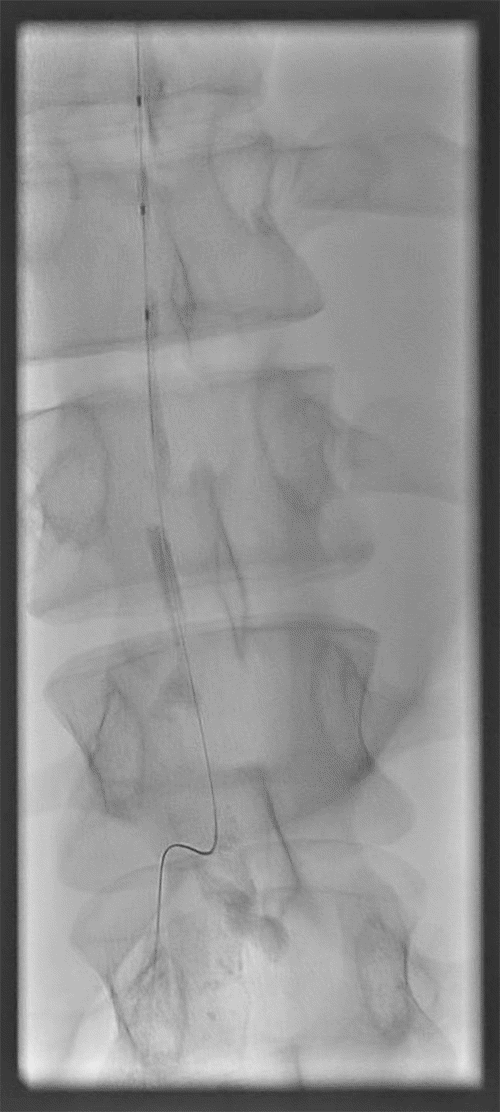

Interventional radiology performed a lymphangiogram to evaluate lymphatic drainage of the pelvic, abdominal, and thoracic regions. The study identified active extravasation from the thoracic duct near the clavicular head. The interventional radiologist then embolized the leaking segment using coils and glue (Figures 3-6). While chest tube drainage briefly declined, it returned to pre-procedure levels by postoperative day 2.

Figure 4. Lymphangiogram via Inguinal Lymph Node Cannulation Demonstrating Opacification of Lumbar Nodes, Cisterna Chyli, and Lower Thoracic Duct. Published with Permission